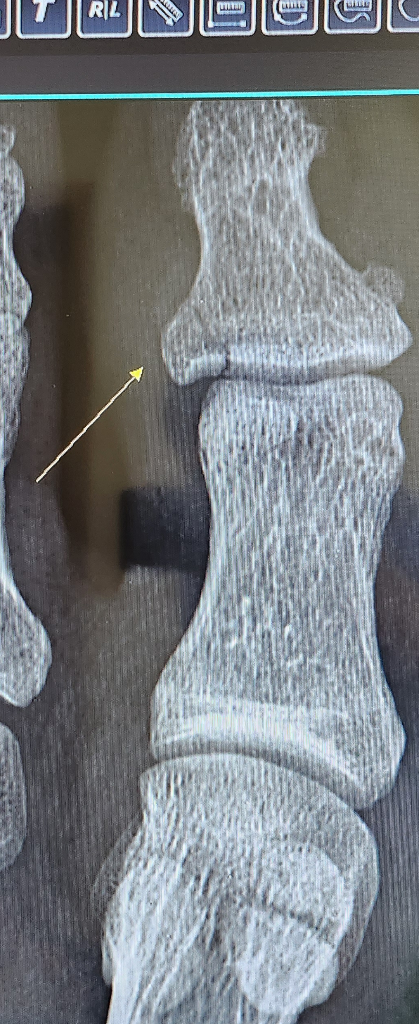

사진과 같은 골절 상태입니다.(무거운물체 찍힘) 지금은 테이핑하고 반깁스 한 상태인데 정형외과 전문의 선생님이 핀 수술을 고려해보는게 좋을것같다고 말씀하시는데. 꼭 해야할까요? 핀 수술할지 고민해보고 연락달라고 하셨습니다. 어제 다치고 바로 병원갔습니다. ㅠㅠ 시간, 돈 들이는게 싫어서 여쭤봐요. 일도 해야하는상황이라(수동 트럭운전) ㅠㅠ 수술의 장, 단점 비수술의 장, 단점도 같이 알려주시면 감사하겠습니다

관절내 골절이 관찰되며 주위에 인대조직에 의해서 벌어질 위험이 있는 부위입니다.

고정만 잘해두시고 활동량을 줄인다면 비수술적 치료도 괜찮아 보입니다.